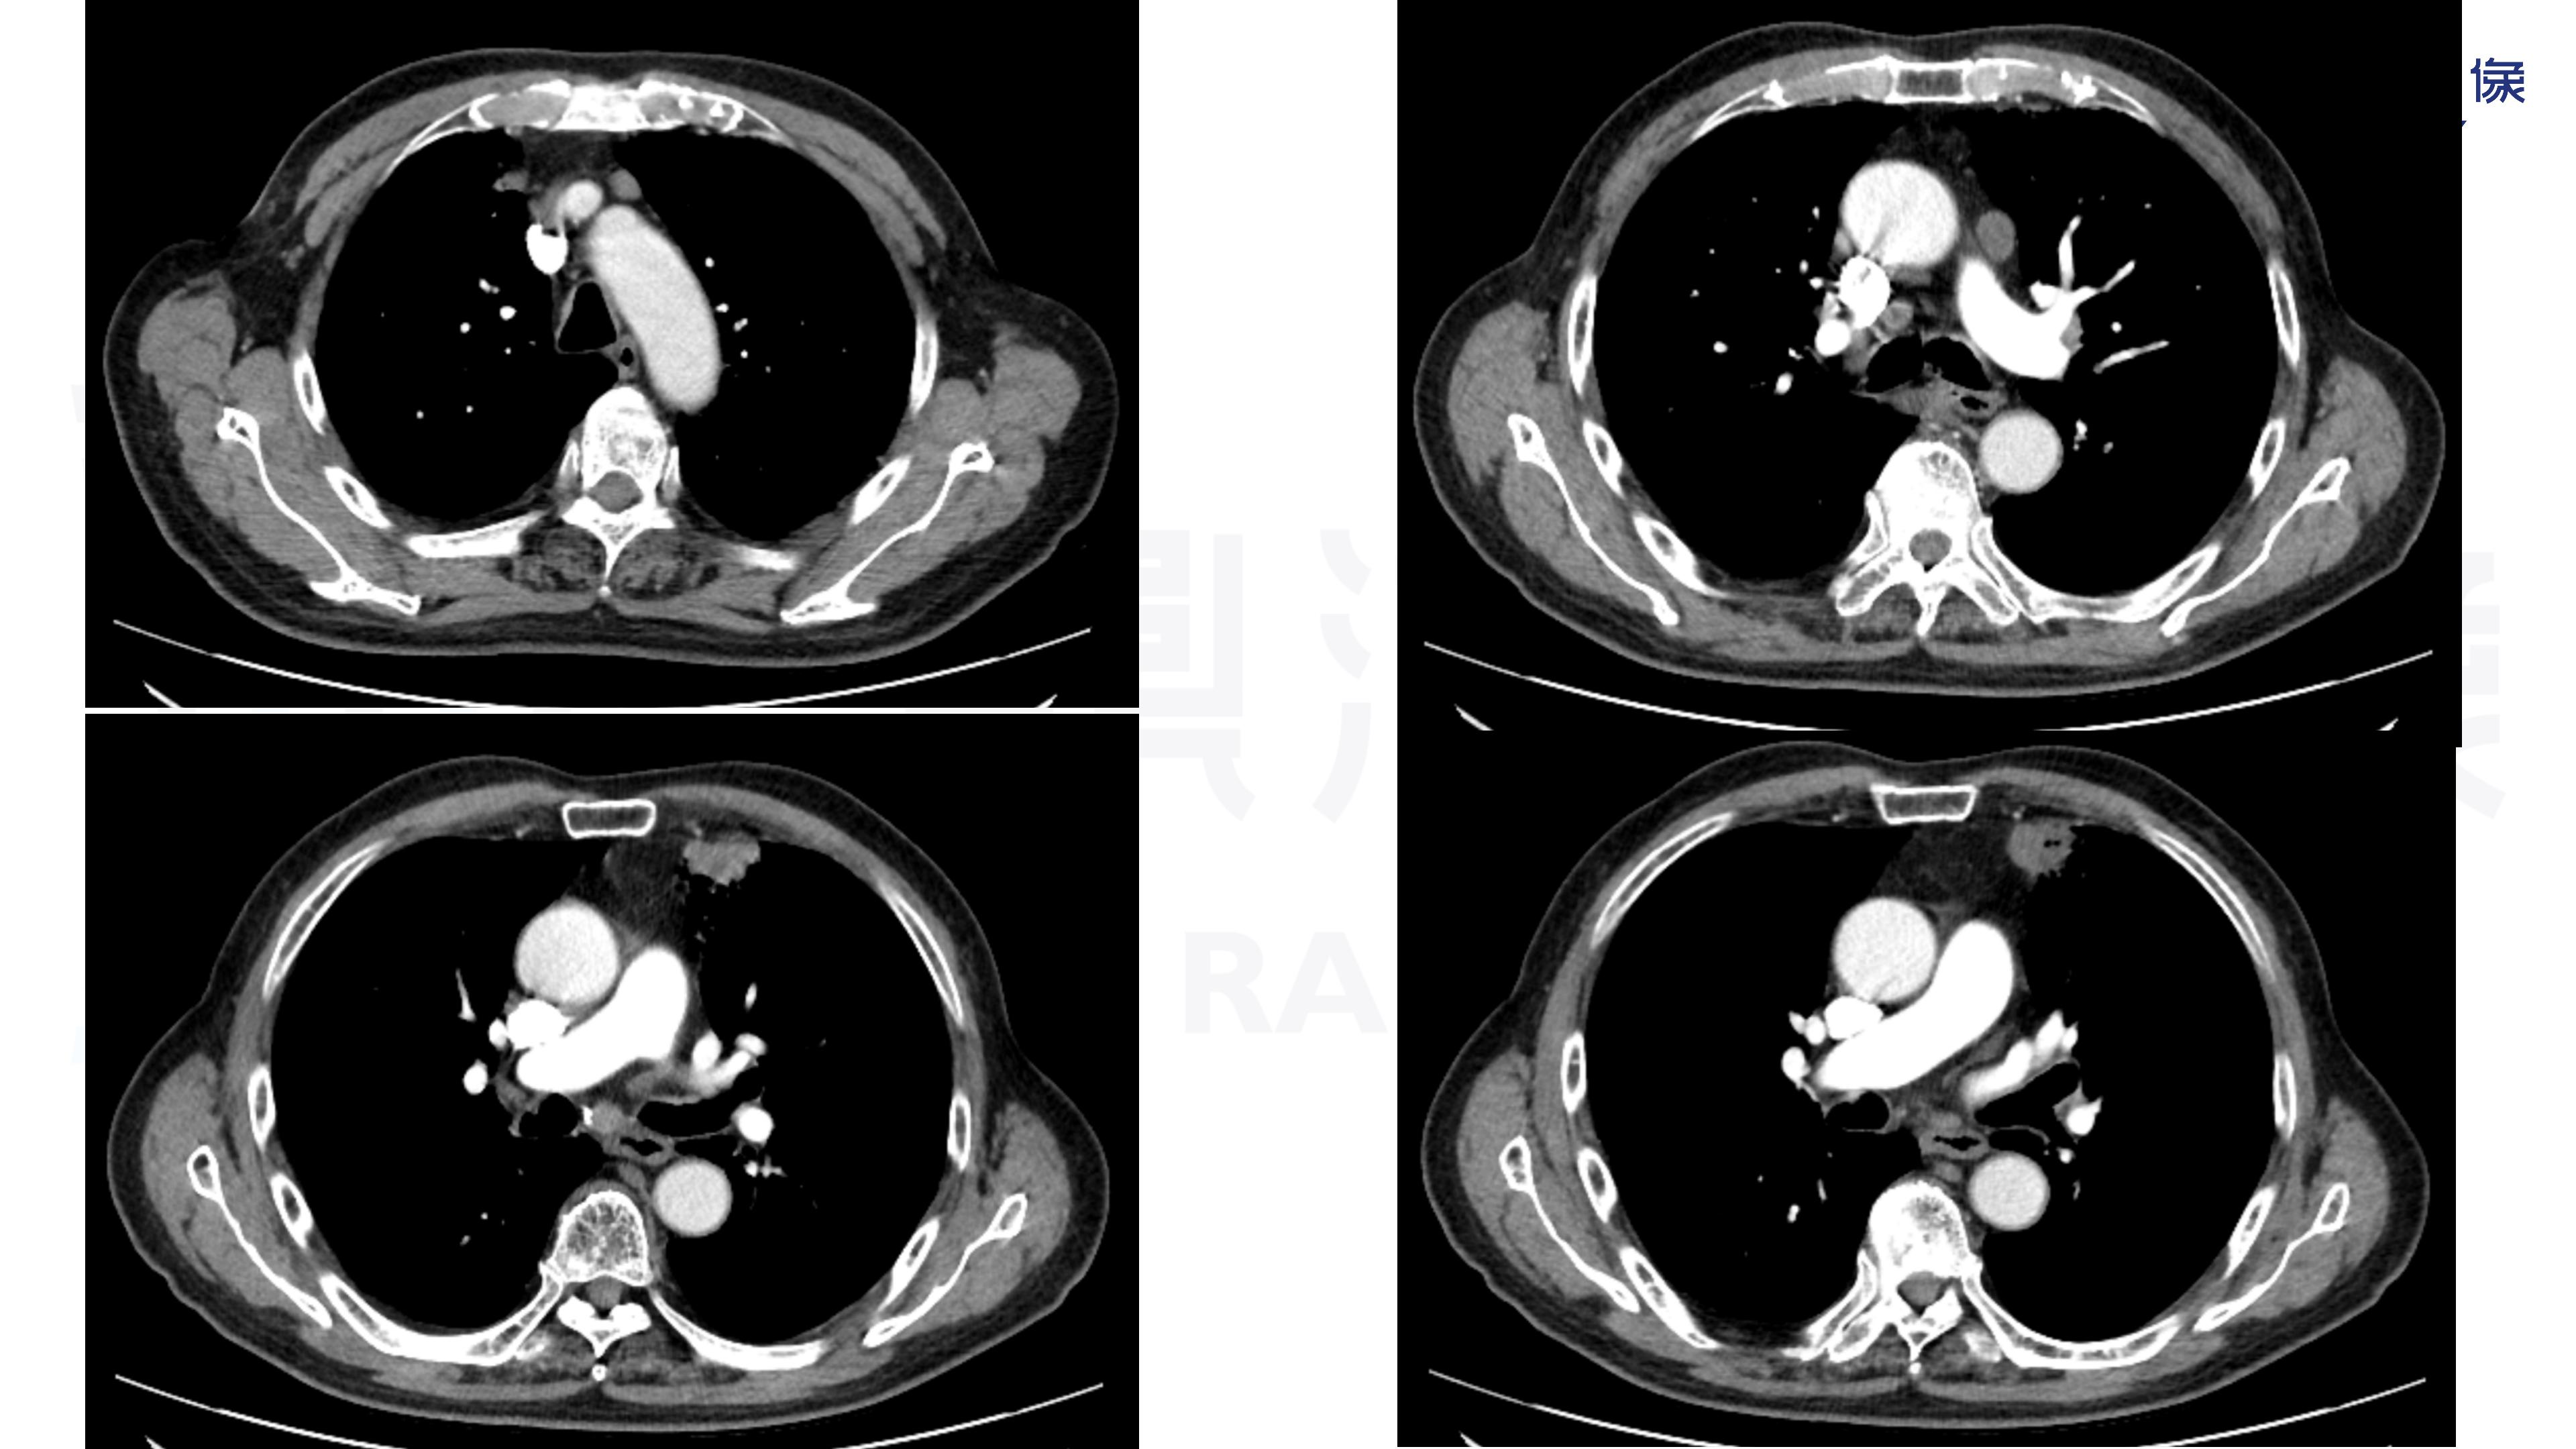

肺腺癌-鼎湖社群读片病例